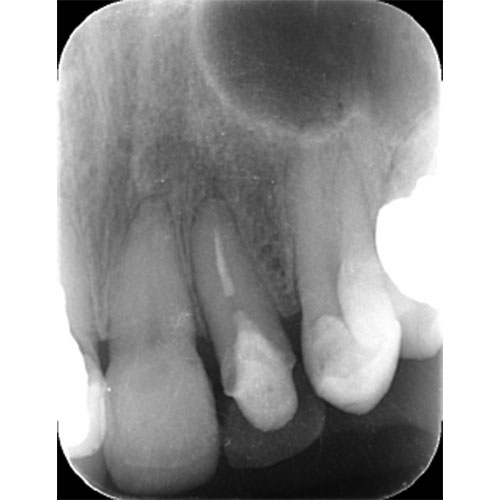

カリエスを取り除くと、遠心の歯質が歯肉縁下になりました。

カリエスが大きく、舌側では歯肉より上に残存歯質がなくなってしまっている。このままではコア、クラウンの接着ができないため、歯を歯肉より上にだすことが重要です。

右の写真では歯肉の上に歯が一周のこり、その上にコアが入っているのがわかります。

左上2は広範囲にわたってCRが充填されているのがわかります。またその周囲に透過像があり、カリエスになっていることもわかります。